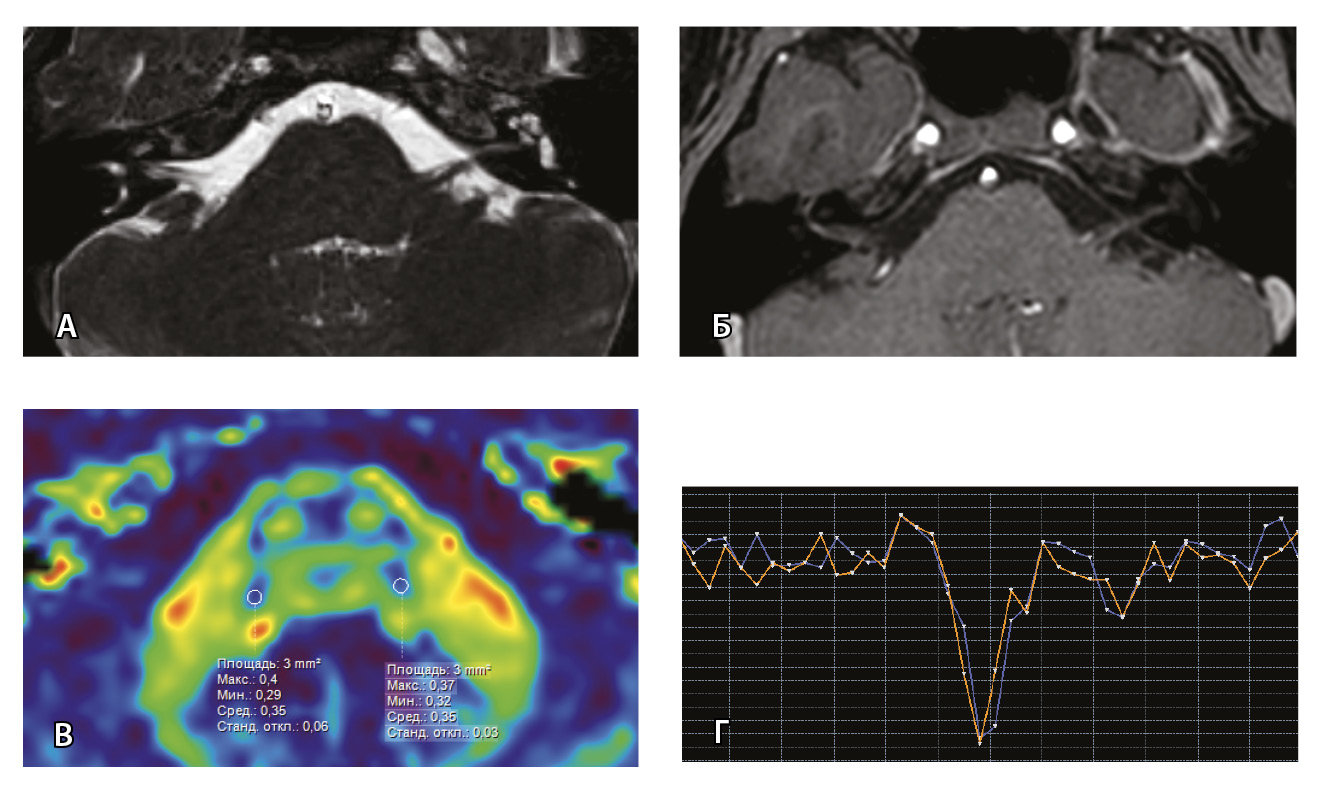

Рис. 7. Клиническое наблюдение 2, пациент 6 лет (А, Б, В, Г). Магнитно-резонансная томография (МРТ) головного мозга: А – прицельная T2-SSFP на область мосто-мозжечкового угла; Б – Т1-взвешенное изображение с контрастным усилением; В – диффузионно-тензорная МРТ (фракционная анизотропия, ФА); Г – Т2*-перфузия. На изображении T2-SSFP отмечается утолщение корешков лицевого, вестибуло-кохлеарного нервов во внутренних слуховых проходах (А, желтые стрелки) и интенсивное накопление ими контрастного вещества (Б, красные стрелки). На уровне моторных ядер лицевых нервов в заднем отделе варолиевого моста значения ФА симметричны (В), признаков гипо-/гиперперфузии не выявлено (Г).

Клиническое наблюдение 3, пациент 13 лет (Д, Е, Ж, З). МРТ головного мозга: Д – прицельная T2-SSFP на область мосто-мозжечкового угла; Е – Т1-взвешенное изображение с контрастным усилением; Ж – диффузионно-тензорная МРТ (ФА); З – Т2*-перфузия. На изображении T2-SSFP патологические изменения на уровне прохождения лицевых нервов во внутренних слуховых проходах не определяются (Д). В медиальном отделе правого полушария мозжечка определяется объемное образование, компримирующее стенку IV желудочка и задний отдел варолиевого моста без признаков васкуляризации (Е). На уровне моторных ядер лицевого нерва в заднем отделе варолиевого моста на изображениях ФА на стороне поражения отмечается минимальное уменьшение показателя ФА до 0,27 (Ж, черная стрелка) и признаки гипоперфузии (З, оранжевый график) по сравнению с контралатеральной стороной (З, синий график)

При этом в клиническом наблюдении № 2 из анамнеза жизни известен ранее установленный диагноз лимфобластного лейкоза в стадии ремиссии. В клиническом наблюдении № 3 значимых анамнестических сведений и данных в пользу атипичного течения ПБ получено не было.

Таким образом, при помощи информации, полученной при проведении МП-МРТ, в обоих случаях был установлен симптоматический характер НЛН, обусловленный развитием неопластических процессов. Оба пациента были направлены в профильные хирургические стационары для проведения дальнейшего лечения.